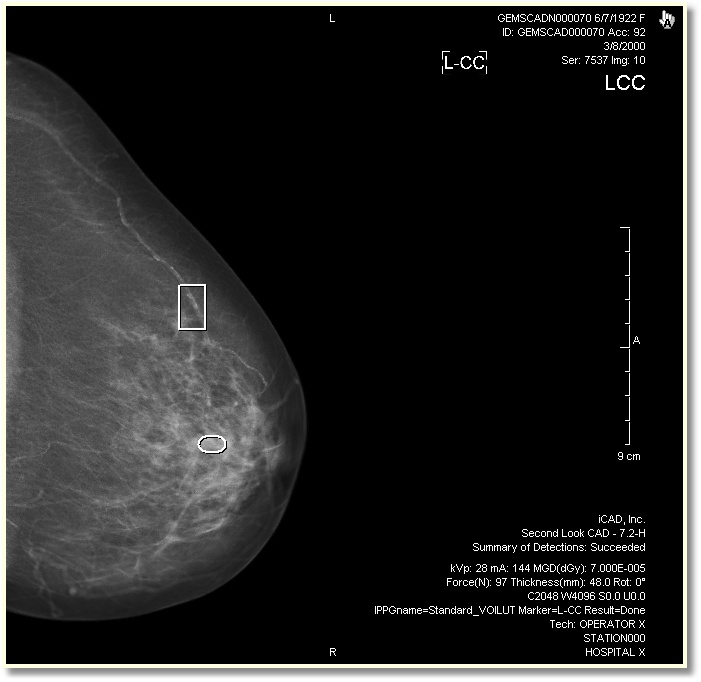

When CAD has been activated from the toolbar, the CAD information will appear as annotations and the markers will appear on top of the image.

There are three types of CAD markers that shows the location of abnormalities:

| Marker | Description |

| Circle/elliptical markers indicate dense areas. | |

| Rectangular markers indicate area that may have micro calcification. | |